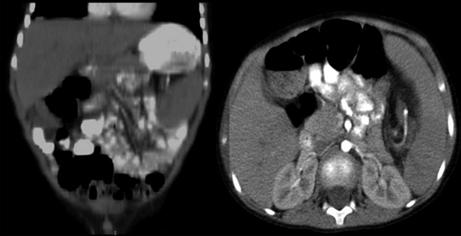

Paciente masculino de 4 años de edad procedente de Guamo (Tolima), con antecedente de cirugía antirreflujo a los 2 años de vida (funduplicatura Nissen (FN) + piloromiotomia anterior) y dolor abdominal crónico estudiado 12 meses previo al ingreso actual, donde se realizó TACc abdominal que evidenció leve esplenomegalia, se descartaron patologías infecciosas o alteraciones hematológicas (Ver Figura 1).

Figura 1 TC de abdomen contrastado realizad a los 3 años de vida con evidencia de bazo con implantación baja y adecuada perfusión esplénica